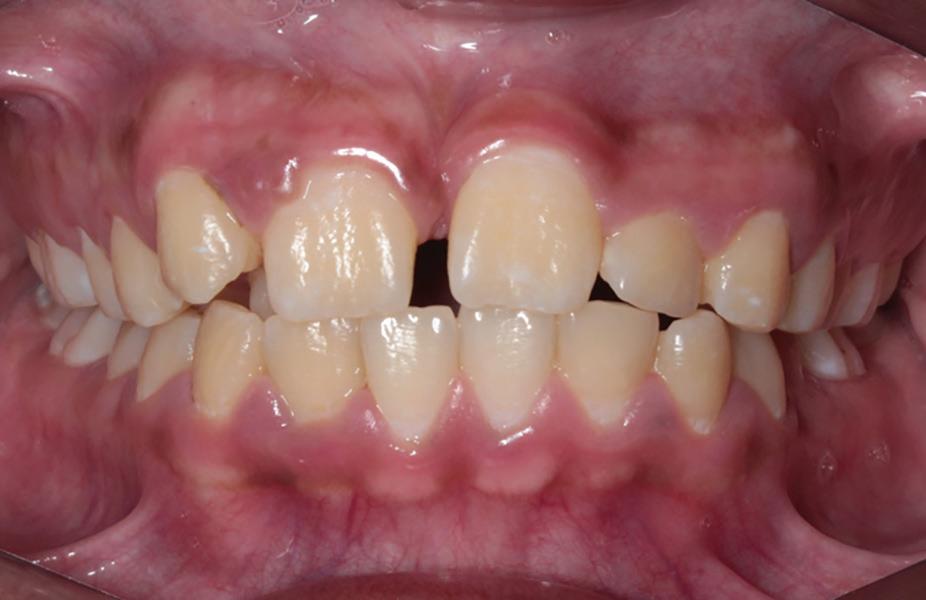

A healthy 10-year-old boy, accompanied by his mother, sought treatment of his mandibular right first molar because of pain in response to cold stimuli but reported no spontaneous pain in this tooth. Clinical examination revealed a carious lesion involving the occlusobuccal surfaces, and the tooth also appeared hypomineralized on the affected surfaces (Fig 1). The tooth responded positively to sensitivity tests, including the electric pulp test and cold test (Endo-Frost, Coltene), and there was no lingering pain or pain on percussion. A preoperative radiograph showed a large carious lesion extending to the pulp, incomplete root formation, and no pathologic periapical lesions (Fig 2). Therefore, the initial preoperative diagnosis was reversible pulpitis. The patient and parent were informed of possible pulp exposure, and VPT treatment after pulp exposure was explained in detail. Written consent for VPT was obtained from the parent.

of a mandibular right first molar with caries affecting the occlusobuccal surfaces, which appear hypomineralized.

Fig 1. Preoperative clinical photograph